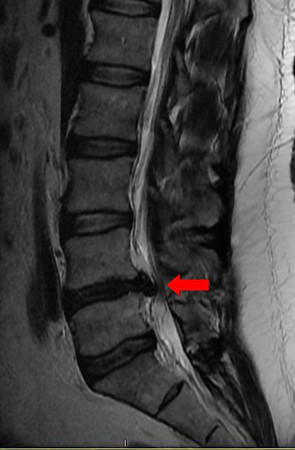

BTW... you'll never know this happened to me.. unless I show you my scars... or you ask me to move your furniture :)

mri-small.jpg

Yeah... that climax resulted in about 3 years of misery, two surgeries, bed ridden for months, and more. To this day I can't really run still.. somewhat of a jog is the closest I can get. Even the bulges at the other 3 adjacent levels would be enough to put most people into long term therapy.

And why I take discussions like 'what happened to all the benches!?!?!' quite personally. I need to be off my feet periodically or I can push myself over the edge and then I can only move like a 80yr old lady for 12-36hrs.

Coasters are marginal for me and I opt out of aggressive stuff to ensure I don't go too hard. No manta for me last trip :/